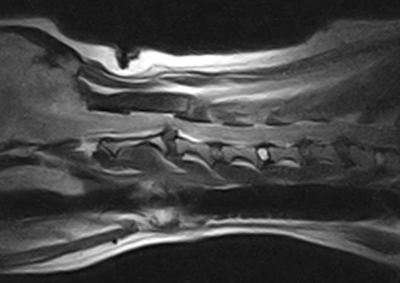

脳神経外科 注意 ボタンをクリックした先に、治療中および手術中の画像が説明で使用されている場合がございます。 そのような画像に弱い方は閲覧なさらないようお願いいたします。 脳神経外科 セメントレス環軸固定術 脳神経外科 Hemi-Laminectomy 脳神経外科 Ventral Slot 脳神経外科 椎体固定術 脳神経外科 Hemi-Laminectomy 脳神経外科 脊髄亜膜下憩室切除 脳神経外科 椎間板ヘルニア G1 脳神経外科 椎間板ヘルニア G2 脳神経外科 IVDD G5 脳神経外科 Ventral Slot 脳神経外科 Ventral Slot 脳神経外科 Ventral Slot 123456> 症例カテゴリー 放射線治療整形外科軟部組織外科脳神経外科内科腫瘍外科救急・集中治療リハビリテーション科腫瘍内科内視鏡科脳神経科呼吸器外科中医・漢方猫の腎移植循環器科電気化学療法